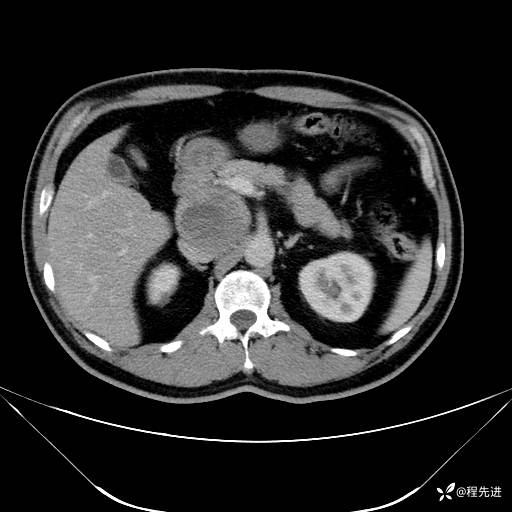

【腹盆】特别精彩病例|发现腹膜后肿物1月余

主诉:发现腹膜后肿物1月余

现病史:患者1月余前查体,行超声检查提示:后腹膜囊实性肿块;慢性胆囊炎伴胆囊内结石;无腹痛腹胀,不伴腹泻发热等;偶感腰背部酸痛。

CT平扫+增强: